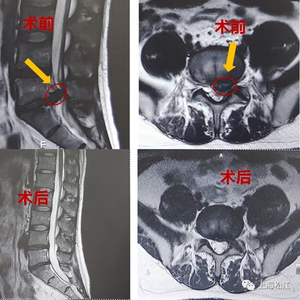

大学毕业后,小吴成为了一名软件工程师,也就是人们常说的程序员。常年久坐在电脑前,小吴体型越来越胖,腰越来越疼,腿部也开始出现疼痛的症状。经医院诊断,小吴腰5骶1腰椎间盘突出,压迫神经根伴有局部钙化。这对年纪轻轻、事业刚刚起步的小吴来说无疑是巨大打击。“不要说上班,我连基本生活起居都有困难。”小吴坦言。

四处就诊无果后,对微创手术将信将疑的小吴来到了上海市第一人民医院脊柱外科“碰碰运气”。而这一来,真让小吴“碰着了”。经胡硕副主任医师初步评估,小吴可以通过保留椎间盘的微创手术方案治疗腰椎间盘突出。“他椎间盘突出部分确实比较严重,突出部分压迫了一侧神经根,并伴有钙化,但是未突出部分退变不严重。微创手术后,配合包括减重、改善坐姿、腰背肌肉锻炼等综合治疗方案,还是可能达到理想的治疗效果。”

不久之后,小吴进行了局麻下的椎间镜手术,术后小吴的腿痛症状消失了,第二天,小吴就顺利出院了。出院后,小吴积极改善生活方式,减重20多斤,平时工作中也注意调整坐姿、锻炼腰背肌,经过长达2年多的随访观察,未出现腰椎间盘突出复发的情况。